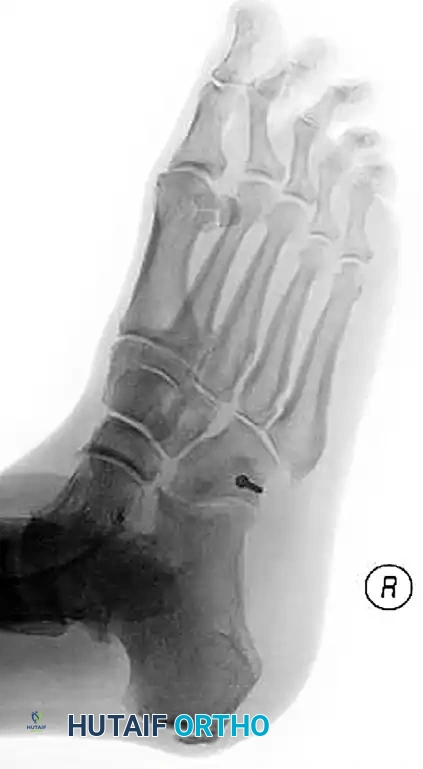

Radiographic Evaluation:

Standard non-weight-bearing radiographs often miss subtle instability. Weight-bearing radiographs are absolute requirements if the patient can tolerate them. If the patient cannot bear weight, a short-leg cast should be applied for 10-14 days, followed by repeat weight-bearing films.

Key radiographic parameters to evaluate:

1. The medial shaft of the 2nd metatarsal must align perfectly with the medial aspect of the middle cuneiform on the AP view.

2. The medial shaft of the 4th metatarsal must align perfectly with the medial aspect of the cuboid on the oblique view.

3. The 1st metatarsal-cuneiform articulation must show no incongruency.

4. The "Fleck Sign": Look for a small bony avulsion in the space between the medial cuneiform and the base of the 2nd metatarsal. This represents a bony avulsion of the Lisfranc ligament.

5. Evaluate the naviculocuneiform articulation for subtle subluxation.

If plain radiographs are equivocal but clinical suspicion remains high, CT imaging is excellent for identifying occult fractures, while MRI is the gold standard for evaluating the integrity of the Lisfranc ligament complex.